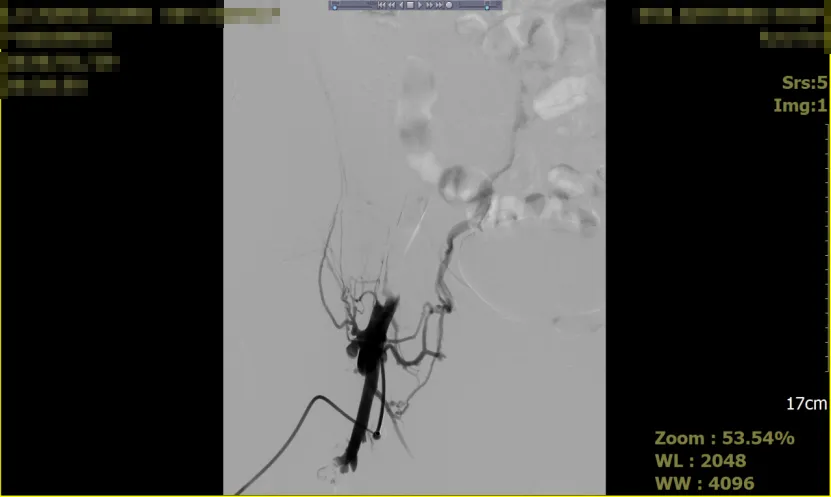

术前影像

为防止血栓进一步迁移及加重症状,采取了介入治疗,具体措施包括:在2026年1月29日夜间,血栓取出,并植入支架以支撑血管通畅。